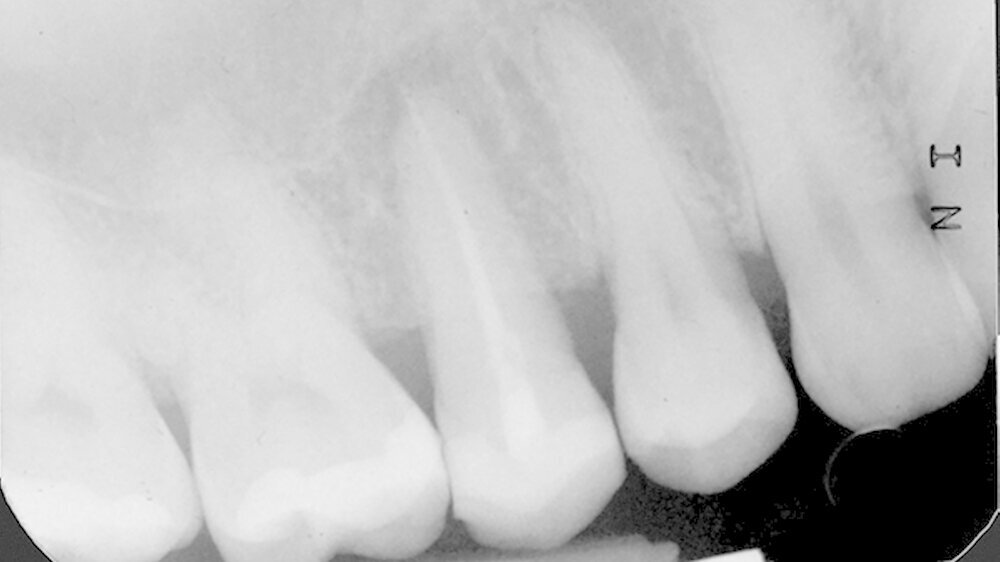

In der Poliklinik für Zahnerhaltung des Universitätsklinikums Münster war zwar die allgemeinmedizinische Anamnese unauffällig, doch zeigte sich klinisch nach Entfernung der vorhandenen mod-Glasionomerzementfüllung ein deutlicher Frakturspalt in mesial-distaler Ausrichtung am Boden der Kavität (Abbildung 1). Darüber hinaus war auf der Röntgenaufnahme des Vorbehandlers eine apikale Aufhellung zu erkennen (Abbildung 2).